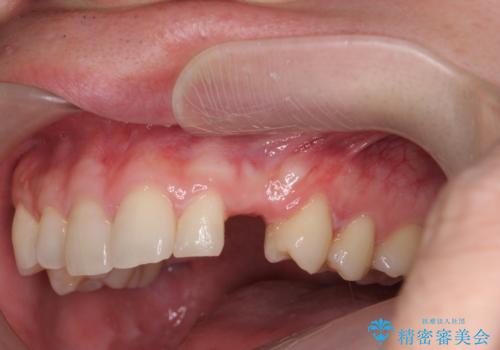

前歯に目立たないノンクラスプデンチャーを作りたい

- 目立つ前歯の欠損の状況を改善されたい、と希望され来院されました。

歯を削らず、インプラント治療でもない方法を希望されたのでバネの目立たないノンクラスプデンチャーを製作します。